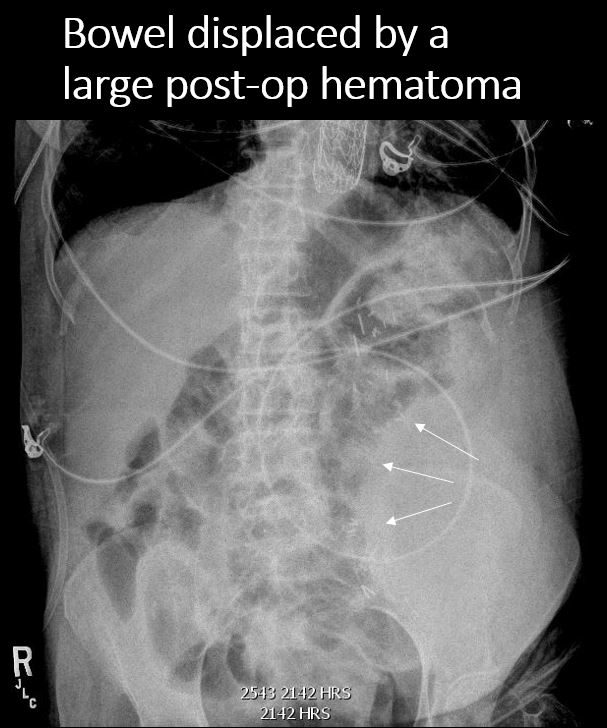

There is displacement of loops of small or large bowel. [Yes/No]